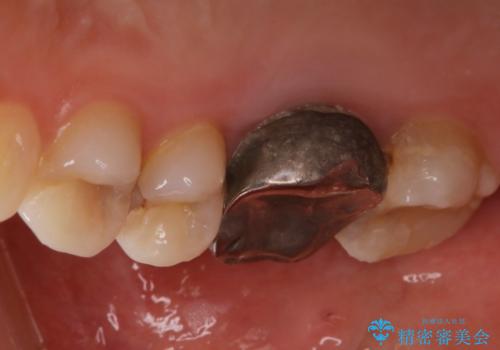

歯の間に食べ物がよく挟まるのを治したい

- 右上4、5間にフロスのひっかかりがあり、レントゲンから隣接面う蝕を確認しました。う蝕除去後は両歯にCADCAMインレーをセットしています。

歯の隣接面を正確に合わせることによって、物が詰まりにくく、再びう蝕になる確率を下げてくれます。